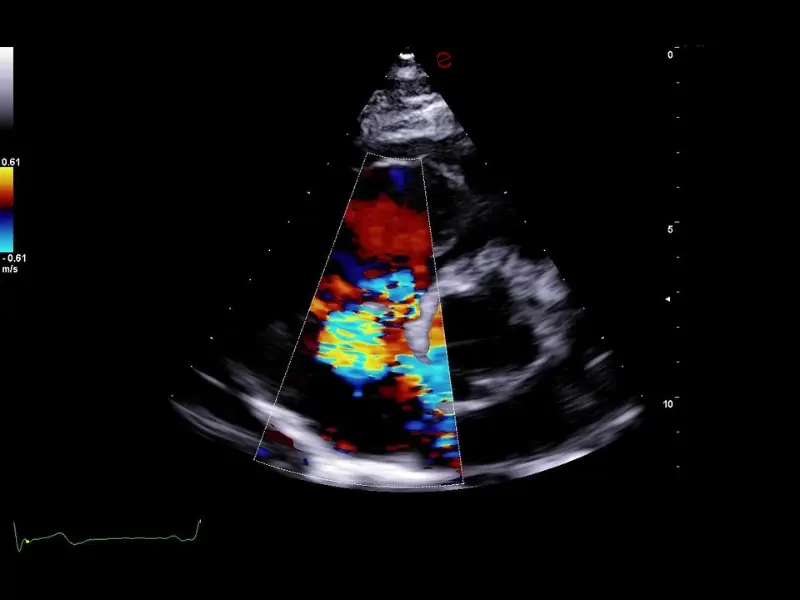

The MyLab™C30 compact ultrasound machine is specifically designed to meet the demands of everyday clinical practice for fast ultrasound access, versatility of use, and space constraints. All this has been achieved without compromising image quality and ultrasound performance. By sharing advanced imaging technologies and transducers with our high-end systems, the MyLab™C30 delivers high quality images and clinical information in a truly compact ultrasound device.

Elevated performance for enhanced diagnostic insights

Featuring the ClearWave Architecture, which combines Esaote’s advanced XBeamforming and XSmart Postprocessing technologies, the MyLab™C30 incorporates state-of-the-art imaging technologies to set a new standard for image quality, giving professionals diagnostic confidence wherever they need it. Maximize the performance of the MyLab™C30 with its wide range of probes for all clinical needs, from daily routine to the most advanced expectations. Equipped with a wide range of advanced features and an accelerated workflow powered by Artificial Intelligence, the MyLab™C30 is your portable ultrasound device that knows no boundaries.